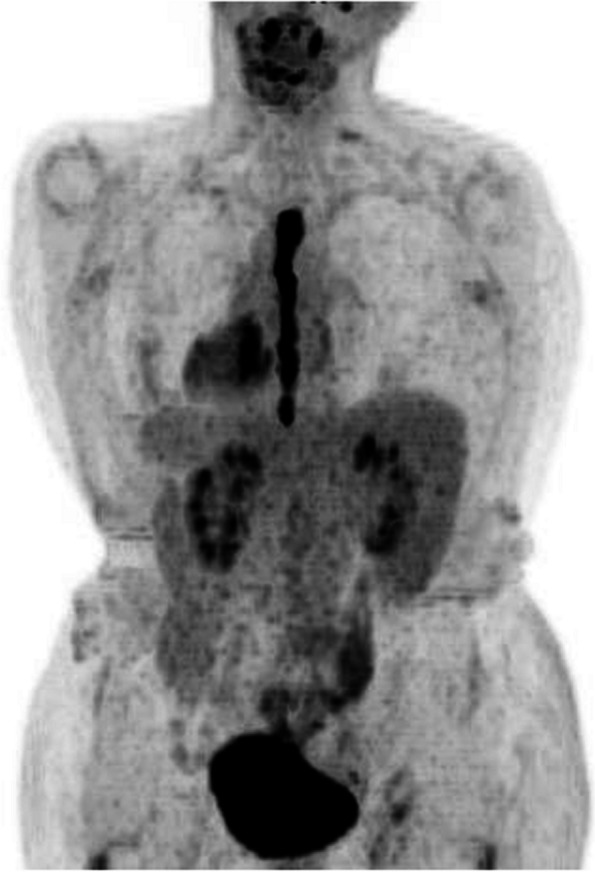

Case presentation: A 44-year-old female presented with fulminant liver failure secondary to inferior vena cava (IVC) thrombosis. Contrast-enhanced computed tomography subsequently revealed a thrombus within the IVC, extending cranially to the right atrium and caudally to the renal veins. The patient's condition, characterized by early comatose symptoms, necessitated surgical intervention. Under extracorporeal circulation, a right atriotomy with thrombus lesion removal and descending thrombectomy of the IVC was performed. Hepatic congestion resolved after the thrombus was removed. A pathological examination of the excised thrombus revealed the presence of high-grade leiomyosarcoma.